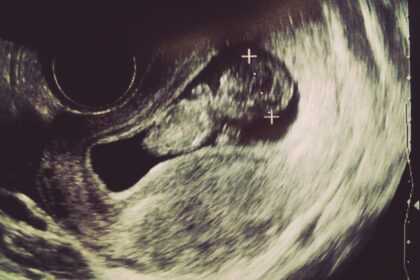

今年は出産予定日と誕生日が近かったので、

誕生日と赤ちゃんどっちが先かなーとか言いながら、そわそわな年でした。